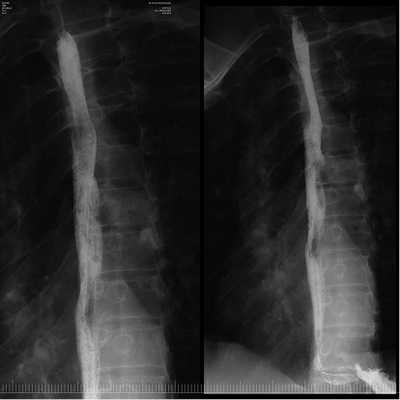

Образование извлечено с помощью эндоскопической петли и направлено на гистологическое исследование. На месте удаленного образования определялся дефект слизистой оболочки до 2 см в диаметре без визуальных признаков повреждения мышечного слоя стенки пищевода (рис. 5). В послеоперационном периоде пациенту рекомендована щадящая диета с исключением грубой пищи, проведена антисекреторная терапия ингибиторами протонного насоса. В 1-е сутки после операции ESD выполнено рентгенологическое контрастное исследование с целью исключения перфорации стенки пищевода с учетом первого опыта диссекции. Затекания контрастного вещества за контуры пищевода не отмечалось (рис. 6, 7).

Рис. 6. Контрастная рентгенограмма пищевода. Затекания контрастного вещества за контуры пищевода нет.

Рис. 7. Контрастная рентгенограмма пищевода. Затекания контрастного вещества за контуры пищевода нет.